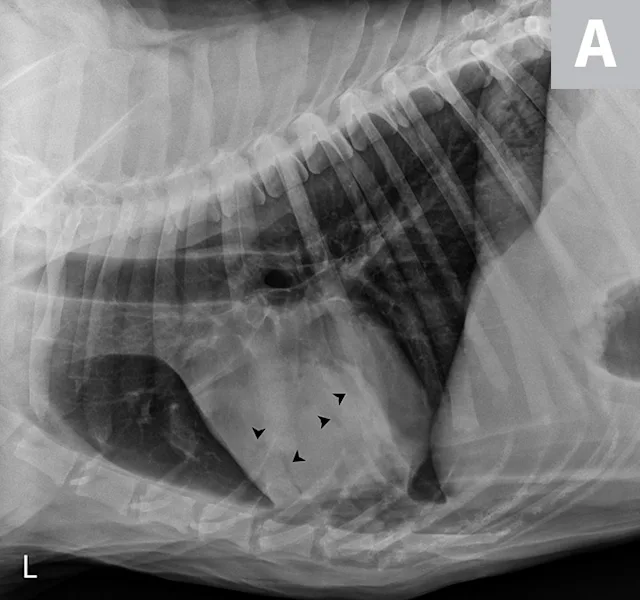

FIGURE 1

Fine-needle aspirate of a cranial mediastinal mass in a 10-year-old spayed schnauzer. Peripheral blood surrounds several irregularly shaped cells with abundant vacuolated cytoplasm and round to irregularly shaped nuclei of variable size (moderate to marked anisokaryosis). These nuclei exhibit finely to coarsely stippled chromatin and occasional prominent nucleoli of variable shapes and sizes. The largest cell is binucleated (arrow), which is a common feature of histiocytic sarcoma.